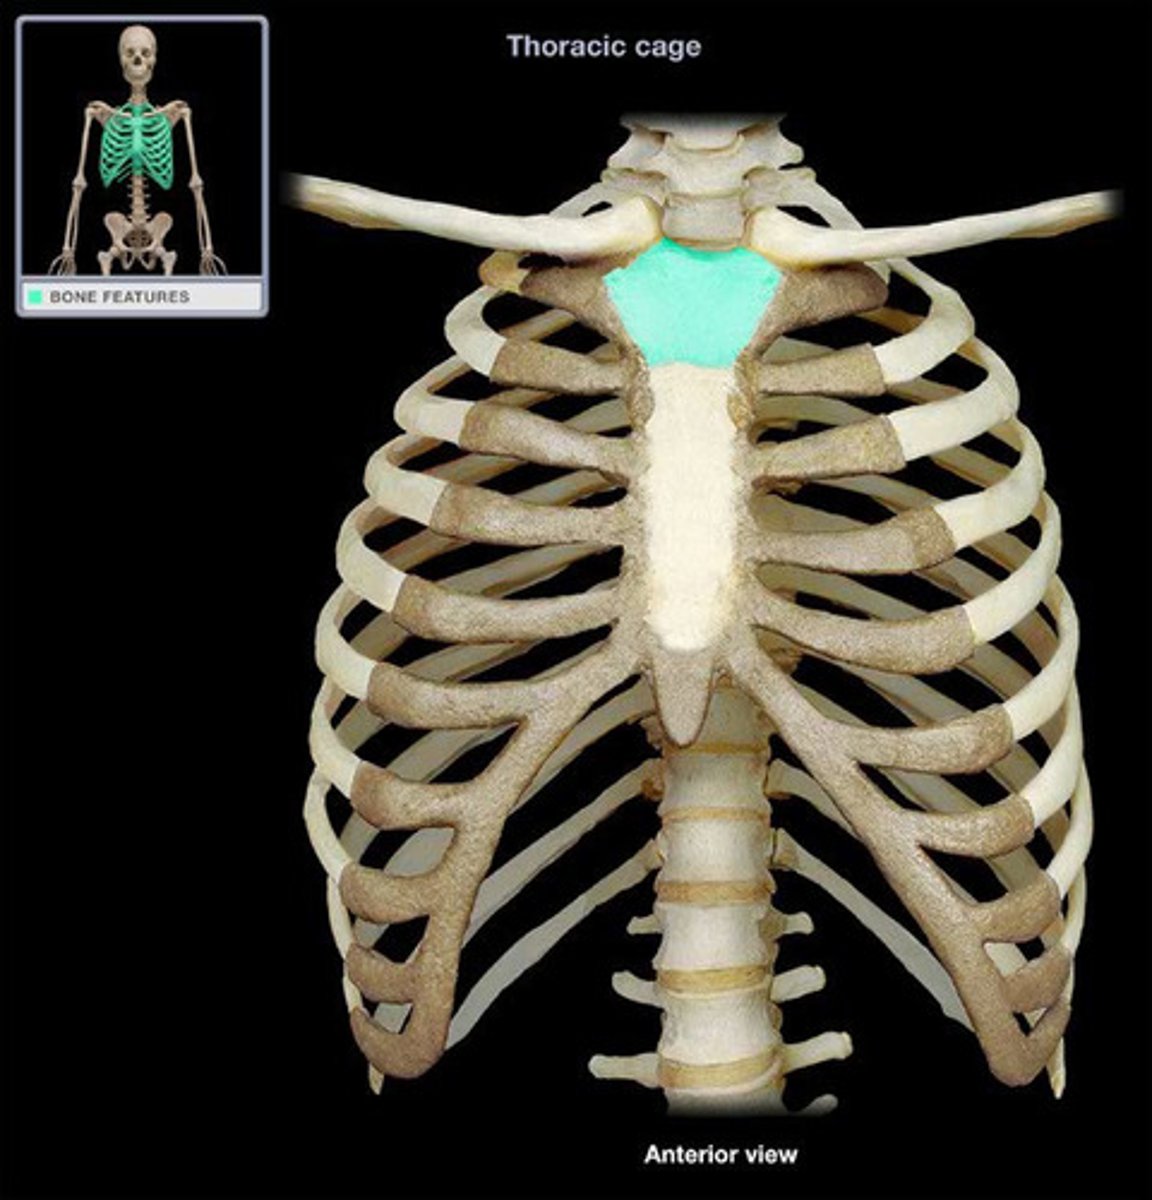

Sternum

Manubrium